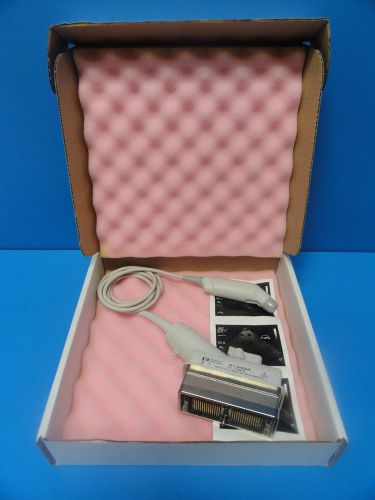

Philips HP R5012 (21349A) Transthoracic Omniplane Sector Probe (SONOS 5500 7500)

PHILIPS HP L7540 / 21258B Linear Array Ultrasound Transducer 4-10 MHz for HP4500

ATL EC 6.5 Ref # PBN-EC-4 -9/10 EV Endo-Cavity Transducer for ATL UM-400 / 400C

GE C364 P/N P9607AB Convex Abdominal / OB-Gyn 3.3 / D2.5 MHz Ultrasound Probe

GE S317 P/N 2116533-2 Cardiac Sector Transducer for GE Logiq 400 / 500 Series